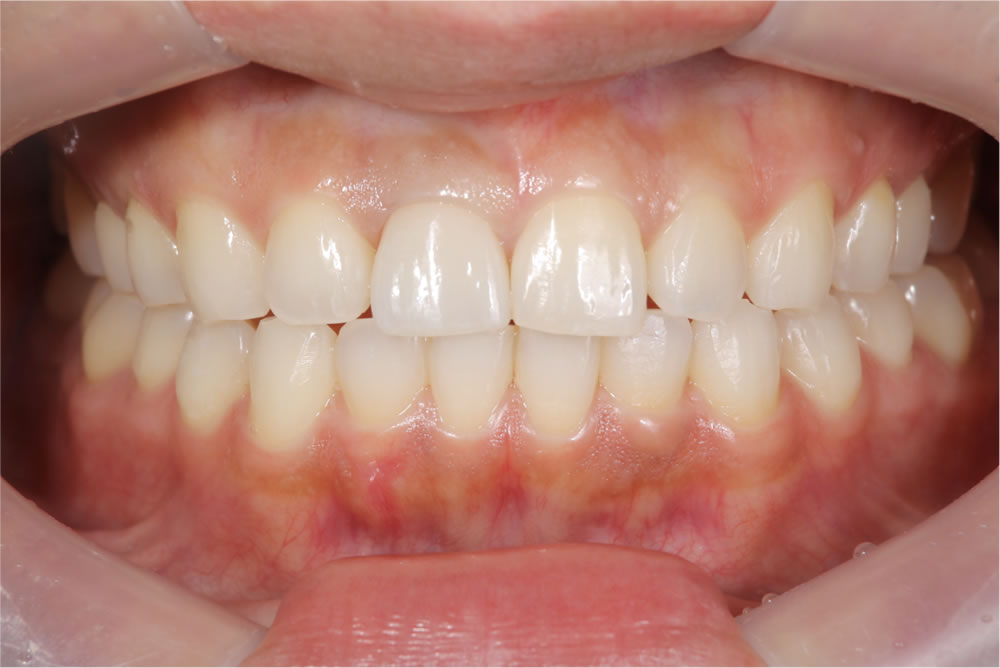

最終のインプラントの上部構造(ジルコニア)を装着

最終のインプラントの上部構造(ジルコニア)を装着し、咬み合わせを調整しました。

治療完了

| 年齢・性別 | 30代 女性 |

|---|---|

| 治療期間 | 6ヵ月 |

| 治療回数 | 10回(前歯インプラント) |

| 治療費 | 前歯インプラント / 517,000円(税込) 矯正 / 605,000円(税込) |